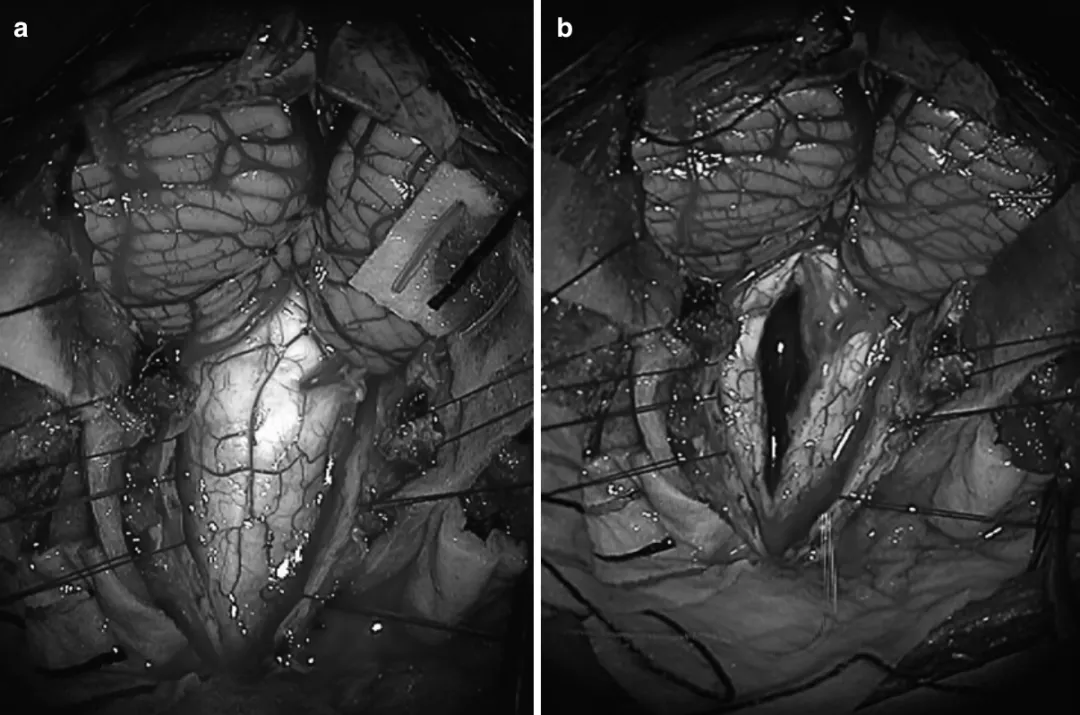

图:延髓-颈髓胶质瘤的术中照片图,(a)后颅窝开颅后,可见延髓-颈髓胶质瘤,在连续的术中神经电生理(IONM)监测下,使用CUSA超声刀切除了肿瘤。(b)显示肿瘤切除后的即时照片,显示脊髓后正中线切开和延髓-颈髓胶质瘤的切除。